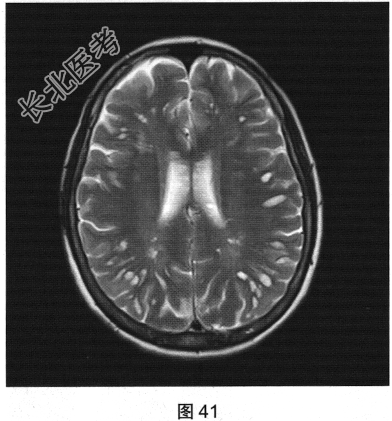

- [材料题] 患者女性,56岁,诉头痛、头晕多年,要求行颅脑MRI检查。查体:神志清楚,问答切题,查体合作。双眼睑无水肿、下垂及闭合不全,双侧瞳孔直径约3.0mm,直接、间接反射均灵敏。双眼视力视野粗侧无异常。发音清晰无嘶哑。耸肩及转头力量对称。四肢活动灵活,肌力、肌张力正常,深浅感觉基本正常;病理征阴性。患者行颅脑MRI检查,如图41~图44所示。

- 多项选择题1.根据患者MRI T1WI和T2WI图像,需要鉴别诊断的疾病有( )

A、多发性硬化

B、脑囊虫病

C、多发腔隙性脑梗死

D、囊性脑室旁白质软化

E、扩大血管周围间隙

F、蛛网膜囊肿